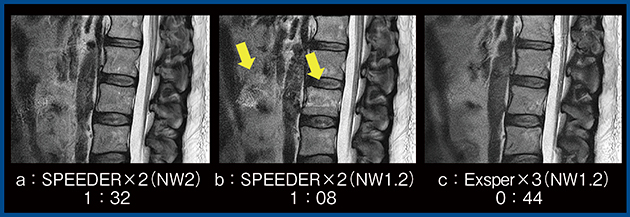

1)Compressed SPEEDER

compressed sensingとparallel imagingを組み合わせた高速撮像技術である“Compressed SPEEDER(CS)”は,本撮像のk-spaceデータを用いて生成したマルチセンシティビティマップを,parallel imagingの展開やcompressed sensingの繰り返し計算に用いることが特徴である。parallel imagingにおけるエンコード依存性を低減するとともに,compressed sensingにおけるランダムノイズやwavelet変換における閾値の低減が図られ,高速イメージングでの画質劣化を防いでいる。

われわれは,AiCEを適用したCSの有用性として,女性骨盤部のT2強調画像において従来法のparallel imagingよりも検査時間を短縮し,画質を改善させることを報告した1)。図2は,実際の子宮筋腫症例のT2強調画像であるが,AiCEを適用したCS(b)では,従来法(a)と比較して撮像時間が短縮するとともに,ノイズが除去され,子宮筋腫がより明瞭に描出されている。結果として,患者負担の軽減や検査の効率化にも寄与すると考える。

図2 AiCEを適用したCompressed SPEEDERと従来法の比較(子宮筋腫)